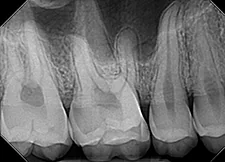

Image Quality

Ultimately, quality is the most important factor in a dental X-ray sensor. A sharp image ensures a proper diagnosis for patients. The Dream Sensor produces easy-to-view, crisp images that work with almost any existing dental software. The results of the direct comparison of DentiMax vs. Dexis are clear.

![]() X-ray taken with the DentiMax sensor shown in Sidexis 4™ software |

![]() X-ray taken with the Dexis™ sensor |